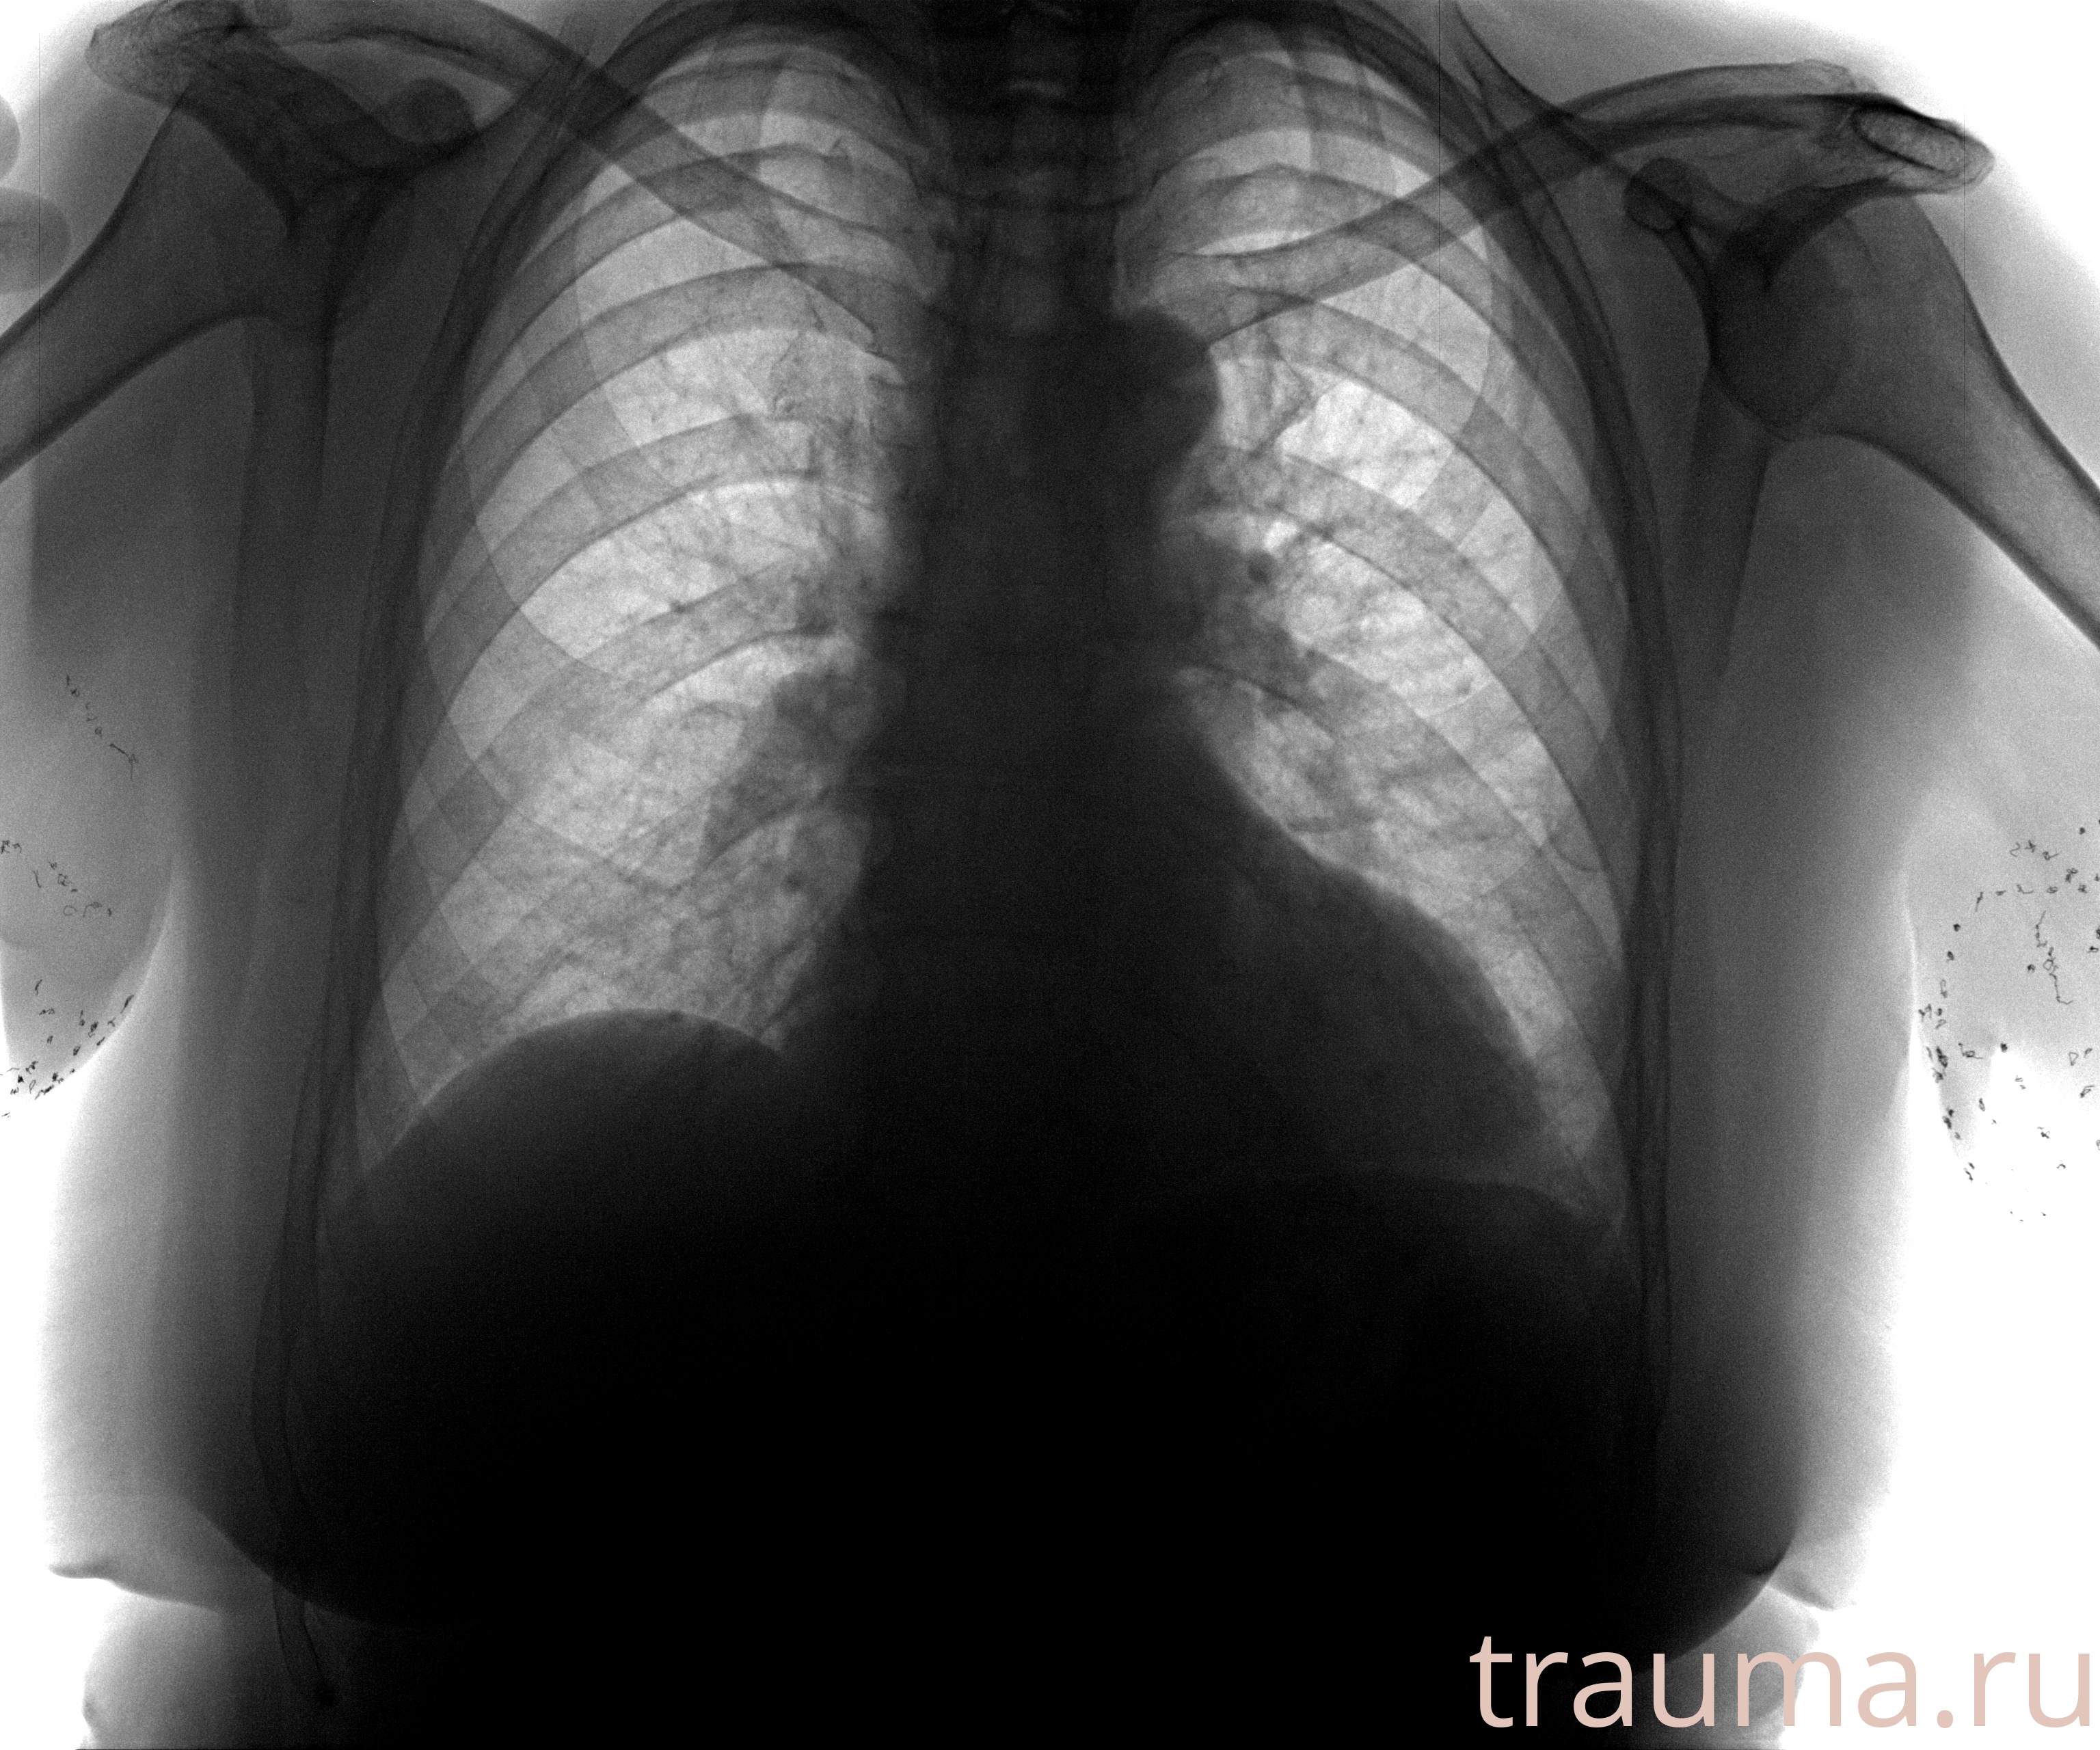

при переломе шейки бедра и пневмонии от компании МосРентген Центр - партнера Института имени Склифосовского

Рентген на дому: по вашему адресу приезжает врач-рентгенолог, травматолог-ортопед с мобильным рентгеновским аппаратом, проводит диагностику травмы или заболевания, делает необходимые рентгенограммы, дает рекомендации по дальнейшему лечению. Получить качественные снимки в домашних условиях возможно благодаря уникальной методике, разработанной МосРентген Центром для института  Склифосовского